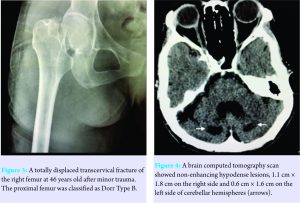

A single 46-year-old Thai woman presented with acute right hip pain after falling onto the ground and could not bear weight. Her underlying diseases were hypertension and mild intellectual disability (IQ=60). At the age of ten, she developed bilateral cataracts and underwent bilateral intraocular lens replacement at the age of about 20. Thereafter, a painless mass gradually developed at the medial side of the left foot and both Achilles tendons became enlarged. At the age of 43, she sustained a left femoral neck fracture owing to a fall in her home and underwent hip hemiarthroplasty (Fig. 1a and b). Her ambulatory status was household independence. A physical examination revealed a thin woman (height 153 cm, weight 38 kg) with her right lower limb in the external rotation position. The left posterior tibial tendon insertion and both Achilles tendons were enlarged in irregular shapes (Fig. 2 a-c). Pes cavus in both feet and camptodactyly of her left little finger were observed. The hip radiographs showed a complete, totally displaced, transcervical fracture of the right femur, Garden classification Type 4 (Fig. 3). The proximal femur appearance was categorized as Dorr Type B. Retention of the well-fixed cementless bipolar prosthesis in the left hip was found. Other bone-surveying radiographs of spine, pelvis, and femurs revealed generalized osteopenia. She underwent hip hemiarthroplasty using a posterolateral approach and a cementless bipolar prosthesis (Avenir Muller stem, Zimmer, Switzerland). There was an accidental crack of the calcar femorale during the stem insertion. A loop of cerclage wiring was then added to prevent fracture propagation. The posterior capsule and short external rotators were repaired. The operative record of the left hip hemiarthroplasty also noted a calcar femorale fracture during the prosthesis insertion warranting cerclage wiring. Cementless bipolar prosthesis (Modular Taperloc stem, Biomet, USA) had been implanted through a posterolateral approach.

Since these clinical findings were largely in line with CTX, investigations for a definitive diagnosis were undertaken with patient consent. An Achilles tendon biopsy was performed, and histopathology confirmed tendinous xanthoma, characterized by lipid crystal clefts surrounded by foamy histiocytes and multinucleated giant cells. Electrocardiography and a chest radiograph were unremarkable. Serum cholesterol, alkaline phosphatase, calcium, phosphorus, and magnesium levels were normal. Testing for serum cholestanol level was not available in our laboratory. Neurological evaluation found good motor function and mild cerebellar ataxia. A brain computed tomography (CT) showed non-enhancing hypodense lesions in both cerebellar hemispheres, with mild cerebral and cerebellar atrophy (Fig. 4).